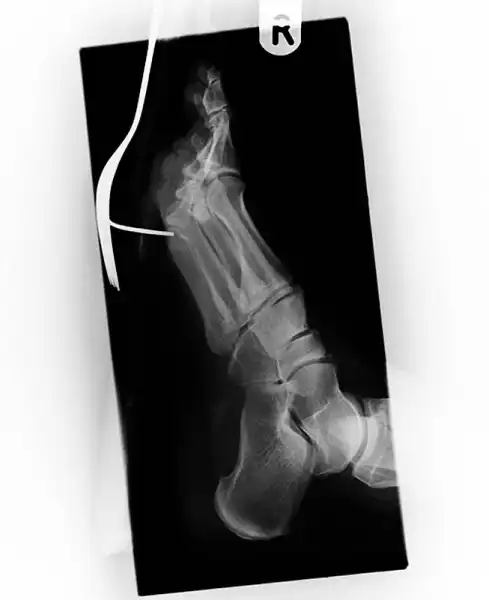

Старинный рентгеновский снимок ступни солдата англо-бурской войны (1899-1902) с огнестрельным ранением. Пуля застряла между большим и вторым пальцами.

Еще один пациент, наступивший на вилку.